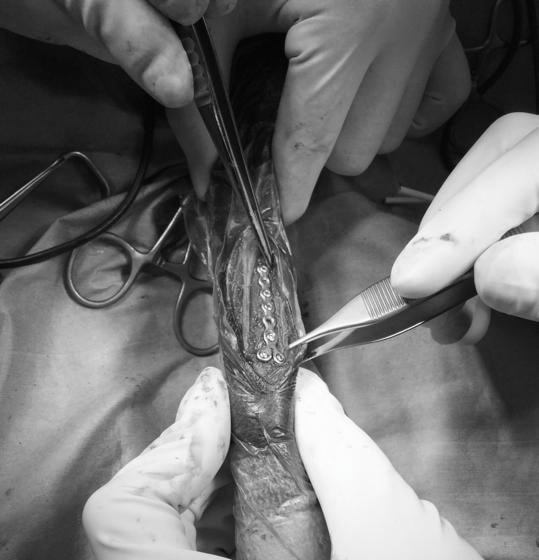

トイプードル 右遠位橈尺骨短斜骨折のALPSによる内固定

症例3:キルシュナーワイヤーのピンニングによる整復

ペルシャ猫 11ヶ月齢 雄

他院にて左大腿骨遠位の成長板骨折(salter-harrisⅠ型)が認められており、治療相談を目的として来院。当院にて、キルシュナーワイヤーを用いたピンニングにより骨折部位の整復を行いました。術後の経過は良好で、現在も経過観察中です。

術前レントゲン

術後レントゲン

Arthrex社のターゲティングデバイスを用いてピンニングの位置を調整することで、確実な固定を行っています。当院ではこの手術器具以外にも、人の手術にも使用される様々な器具を導入し、手術精度を高め、また医療メーカーと新しい器具の開発、試作にも取り組んでおります。